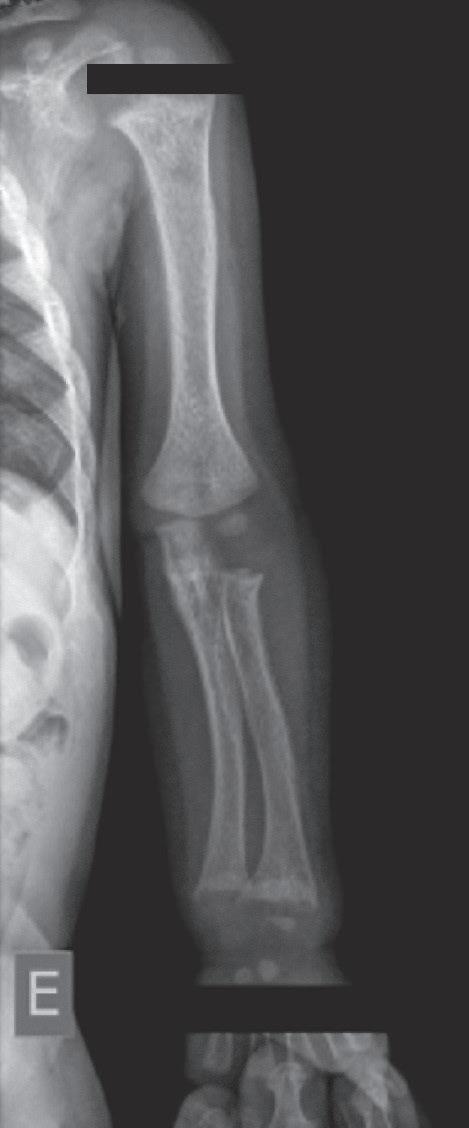

calcificação provisória na interface metáfise/epífise. Posteriormente, ocorre desorganização progressiva da placa metafisária, que se apresenta côncava, alargada, limites irregulares e franjeados, constituindo o sinal da taça (Figura 38.2).

Os achados típicos são rarefação óssea generalizada e alterações na placa de crescimento, que alcançam diferentes graus de gravidade em relação à perda dos limites, franjeamento das bordas metafisárias, concavidade e distanciamento entre a metáfise e a epífise. Na osteomalácia pode haver adelgaçamento da cortical dos ossos longos e pseudofraturas (zonas de Looser), mais frequentes em colo de fêmur, omoplata e púbis.5-7

A gravidade do raquitismo pode ser analisada a partir do escore de gravidade do raquitismo.8 Essa é uma escala de pontos (de 0 a 10 no total) obtida pela análise das alterações radiológicas observadas nas placas de crescimento dos punhos (rádio e ulna distais) e do joelho (fêmur distal e tíbia proximal), avaliando-se o grau de irregularidade, de concavidade e da extensão afetada da placa de crescimento.

Figura 38.2   (A a C) Achados radiológicos característicos em pacientes com raquitismo. Sexo feminino, 8 anos de idade, raquitismo calciopênico por deficiência da 25-hidroxilase (mutação no gene CYP2R1), observa-se alargamento das junções costocondrais (rosário raquítico) (A ). Sexo feminino, 2 anos de idade, raquitismo hipofosfatêmico ligado ao X (mutação no gene PHEX), observam-se rarefação óssea difusa, placas de crescimento dos membros superiores e inferiores com limites mal definidos, alargadas; metáfises distais do rádio e ulna com bordas côncavas (sinal da taça) e maior distanciamento entre metáfise e epífise (B e C)

Fonte: imagens pertencentes ao autor.